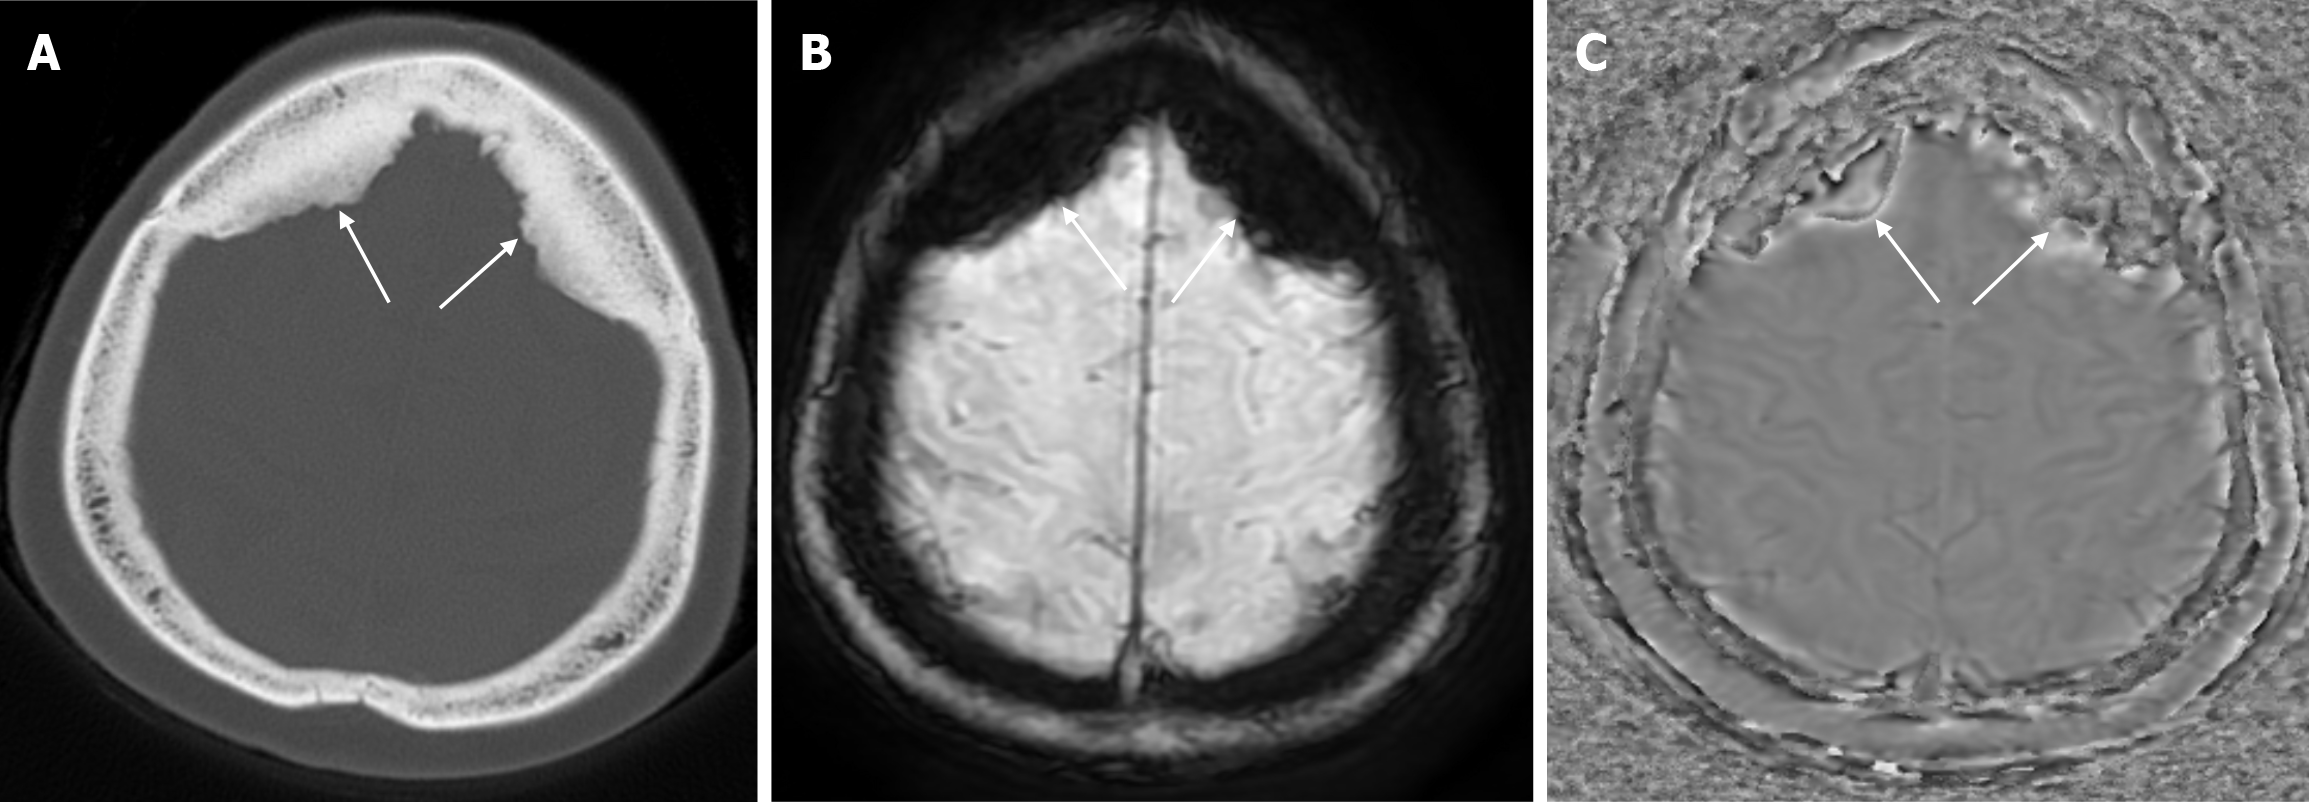

Small parietal foramina (approximately 1-2 mm in diameter) are intramembranous bone development defects that occur in 60% to 70% of the population. The parietal foramina close during the fifth month of normal embryonic development and give rise to emissary veins that anastomose with the superior sagittal sinuses. Enlarged parietal foramina (> 5 mm) occur at a rate of 1:15000 to 1:50000. These parietal/biparietal foramina arise as a result of abnormal calvarial ossification around the parietal notch during fetal development. At birth there is a large single midline or bilateral calvarial defect with the brain covered by the dura, pericranium and overlying scalp. Individuals with enlarged parietal foramina present with symptoms of severe headache, vomiting and intense pain when mild pressure is applied to the unprotected cerebral cortex. Parietal foramina may rarely be seen together with craniofacial and skeletal anomalies, myelomeningocele, and encephalocele. Genetic studies have shown a familial occurrence with autosomal dominant inheritance. Mutations in the MSX2 and ALX4 genes have been reported in almost 80% of parietal foramina cases[16]. CT scan shows single or double rounded defects in the parietal bone adjacent to the intersection of the sagittal and lambdoid sutures. The defects may be large and confluent along the midline. MRI is the preferred method to detect venous, cortical or meningeal abnormalities associated with the parietal foramina[14].

Leptomeningeal cysts can develop as a rare complication of linear skull fractures in children. The incidence is reported in the literature to be between 0.05% and 0.1%. They are usually seen in children under the age of 3. These cysts most commonly occur in the cranial convexity but can also be seen in the posterior fossa and orbital roof. This complication develops as a result of dural tear associated with skull fracture. Laceration of the dura mater leads to herniation of the leptomeninges and filling with CSF. The continuous pulsatile pressure of the CSF and the expansion of the cyst cause resorption of the adjacent bone, erosion of the bone edges and expansion of the skull fracture. The fracture site, together with the thickness of the soft tissues, can be seen on plain radiography. While bone fractures can be better demonstrated with CT imaging, MRI is more useful in distinguishing leptomeningeal cysts from other pathologies. Leptomeningeal cysts are isointense with cerebrospinal fluid on both T1-weighted and T2-weighted images (Figure 10). Associated pathologies such as subdural fluid collections, hematomas, encephalomalacia, and ventricular dilatation may also be seen on CT imaging and MRI. Early diagnosis is important because of the risk of neurological deterioration and seizures, and treatment includes dural repair and cranioplasty[35].